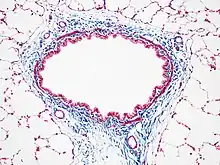

Masson's trichrome stain of rat airway. Connective tissue is stained blue, nuclei are stained dark red/purple, and cytoplasm is stained red/pink.

Most recipes produce red keratin and muscle fibers, blue or green collagen and bone, light red or pink cytoplasm, and dark brown to black cell nuclei.